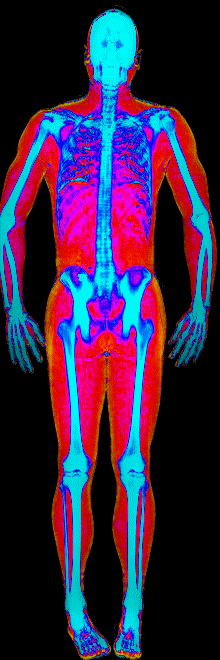

A DEXA scan passes two low-dose X-ray beams through your entire body, head to toe. Different tissues absorb different amounts of energy: bone absorbs the most, muscle and lean tissue less, and fat the least. The scanner reads how much energy made it through every pixel and assigns each one to a tissue type.

The colorful image at the top of every BodyStats DEXA report is literally that map. Bone shows up in cyan and white. Lean tissue is red. Fat is yellow and orange. Your body-fat percentage isn’t an inference — it’s a count of how much of that image is yellow and orange, broken out region by region: left arm vs right, left leg vs right, trunk, android (belly), gynoid (hips). And visceral fat — the dangerous abdominal fat that bioimpedance can’t see at all — comes back as its own number in cm².

This page features real, anonymized DEXA scan images from BodyStats clients, organized by gender and body fat percentage in 5% increments. DEXA (Dual-Energy X-ray Absorptiometry) is the clinical gold standard for measuring body composition — far more accurate than scales, calipers, or visual estimates.

Each colorized scan shows the distribution of fat tissue (shown in warmer colors) and lean tissue (cooler colors) throughout the body. Compare your own DEXA scan to others in your range, or see what different body fat levels actually look like on a scan.

Female DEXA Scans by Body Fat %

25 to 30% body fat